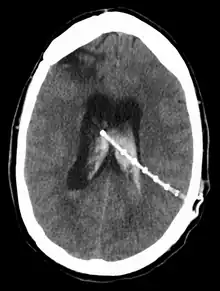

Une dérivation du liquide cérébrospinal (ou shunt cérébral) est un dispositif implanté de façon permanente à l’intérieur de la tête et du corps pour évacuer l’excès de liquide du cerveau. Elle est couramment utilisée pour traiter l'hydrocéphalie, le gonflement du cerveau dû à une accumulation excessive de liquide céphalo-rachidien (LCR). Si rien n'est fait, l'excès de LCR peut entraîner une augmentation de la pression intracrânienne (PIC), ce qui peut provoquer un hématome intracrânien, un œdème cérébral, un écrasement du tissu cérébral ou une hernie[1]. Le drainage assuré par une dérivation peut atténuer ou prévenir ces problèmes chez les patients souffrant d'hydrocéphalie ou de maladies associées.

L'emplacement de la dérivation est déterminé par le neurochirurgien en fonction du type et de l'emplacement du blocage provoquant l'hydrocéphalie. Tous les ventricules cérébraux sont candidats à la dérivation. Le cathéter est le plus souvent placé dans l'abdomen, mais d'autres emplacements incluent le cœur et les poumons. les dérivations peuvent souvent porter le nom de la voie utilisée par le neurochirurgien. L'extrémité distale du cathéter peut être située dans à peu près n'importe quel tissu comportant suffisamment de cellules épithéliales pour absorber le LCR entrant. Ci-dessous quelques plans de routage courants pour les dérivations cérébrales :